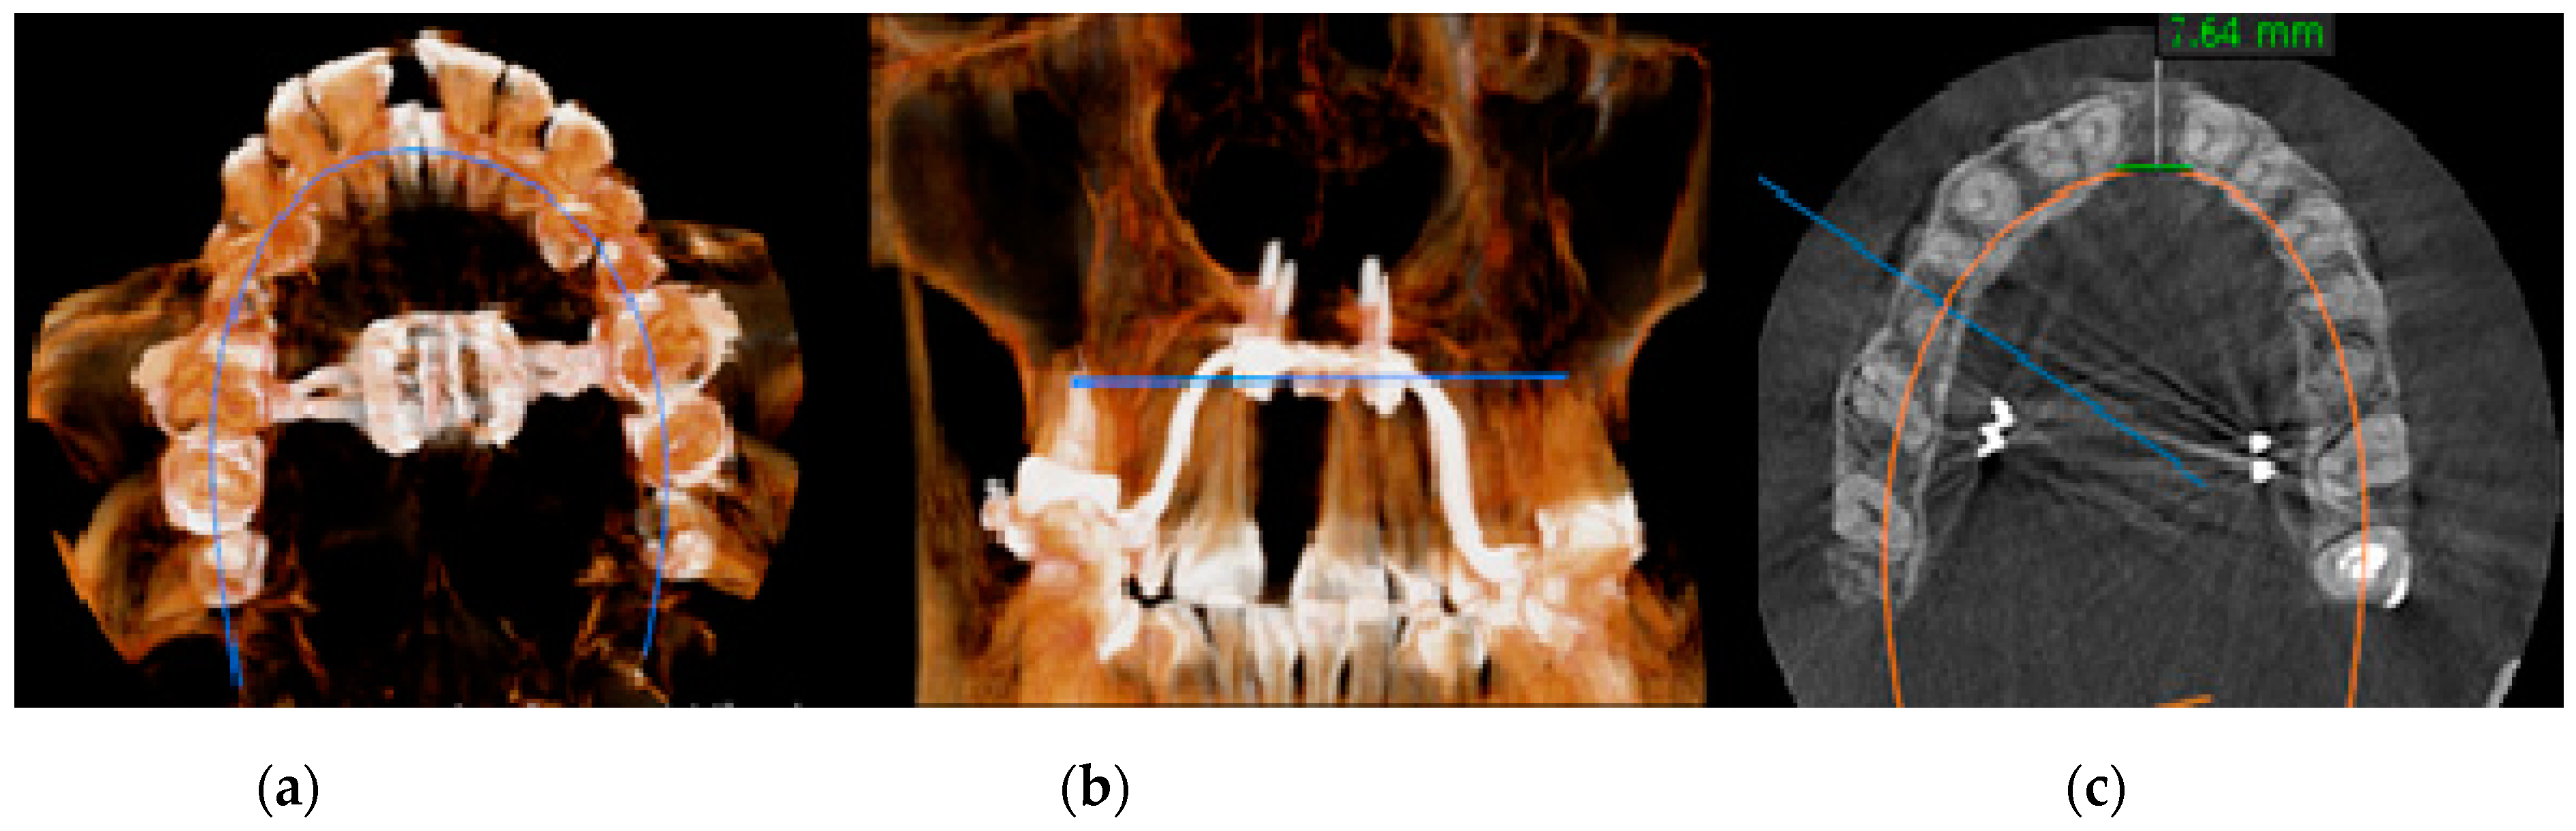

- MARPE associated with cortico-puncture therapy efficiently split the midpalatal suture in adults. The mean split at the anterior nasal spine (ANS) and posterior nasal spine (PNS) was 3.76 and 3.12 mm, respectively. The magnitude of the split at the PNS was smaller than at the ANS (by approximately 85% of the distance), showing that the opening of the midpalatal suture was almost parallel in the anteroposterior direction.

| Parameter | Interincisal Opening at the CEJ Level/Millimeter |

|---|---|

| Minimum | 3.360 |

| 25% percentile | 3.783 |

| Median | 4.210 |

| 75% percentile | 4.365 |

| Maximum | 4.770 |

| Mean | 4.103 |

| SD | 0.3881 |

| SEM | 0.08679 |

| Lower 95% CI of mean | 3.921 |

| Upper 95% CI of mean | 4.284 |